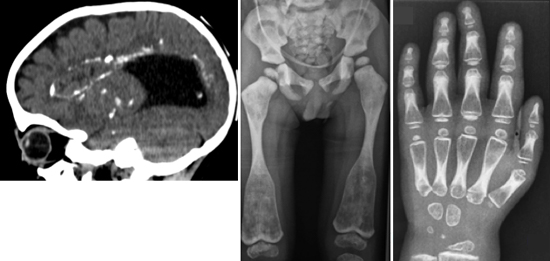

図1 骨と脳を侵す新たなタイプの難病の表現型

- 1: 脳のCT像(側面像)。脳室の拡大(脳内黒い部分)と脳内の多数の石灰化(白い部分)が見られる。

- 2: 脳のMRI像(冠状断)。脳の萎縮、脳室周囲の神経変性を示す高信号領域(白矢印)が見られる。

- 3: 脊椎椎体のX線像。椎体の扁平化と硬化が見られる。

- 4: 骨盤・下肢のX線像。骨の濃度の増加が見られ、大腿骨骨幹端部の拡大(白矢印)が特徴的である。

- 5: 手の骨のX線像。骨の濃度の増加が見られる。

研究チームは、最近収集した難病患者の中に、共通の骨格、脳神経系の異常を持つ3家系7人の患者を発見しました。骨格には、全身の骨硬化(骨の濃度の上昇)、脊椎の形成異常、長管骨と短管骨の骨幹端部の拡大などの特徴的な異常が、脳には、脳室(脳内部にある脳脊髄液で満たされている空間)周囲の石灰化を伴う白質脳症[9]様の神経変性とダンディ・ウォーカー奇形[10]などの脳奇形が認められました(図1)。このような骨格、脳神経系の異常の組み合わせは過去に報告がなく、新たな症候群であると考えられました。そこで、研究チームはその原因遺伝子の同定を試みました。